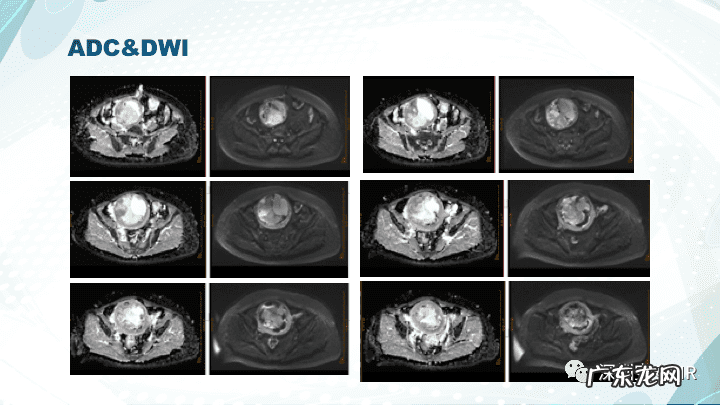

【子宫内膜间质肉瘤病理 子宫内膜间质肉瘤分期标准】下载放射沙龙app,获取更多影像科学习资料,更多学习视频等着你哦